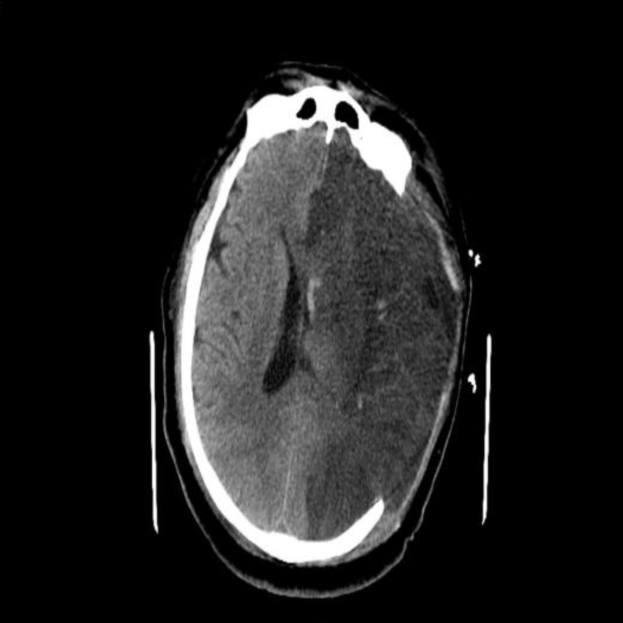

术后即刻

术后3h

术后1天

术后3天CT

术后6天CT

术后11天CT

这是一例大核心梗死超时间窗急性AIS病人中间导管抽吸联合支架取栓病例。患者最后正常时间距离就诊时间约7.5小时。目前对于超时间窗急性脑梗死患者血管再通治疗指征,组织窗及灌注检查非常重要,通过灌注检查可以判断是否存在大面积低灌注区域并及时恢复血流,成为血管再通治疗是否获益的关键。经术前颅脑CT、MRI及DWI评估,提示左侧脑组织大范围核心梗死,DWI及FLAIR明显不匹配,如果取栓血管再通后,能挽救部分缺血半暗带,但再通后脑组织高灌注水肿、出血风险较大,应充分认识到取栓术后短时间内二次手术去骨瓣减压可能性较大。对于大梗死核心的取栓手术指南没有明确推荐,但有部分病人手术后明显获益。该患者年轻,家属积极,术前充分与患者家属沟通,机械取栓及去骨瓣手术协议书一并签署。本例患者颈内动脉末端急性闭塞,易形成大负荷量血栓,单纯支架取栓容易造成血栓逃逸,造成远端血管栓塞。先使用心玮Extraflex远端通路导管抽吸,再使用SWIM技术拉栓及抽吸同步进行,可以有效避免该情况发生。术中支架拉出绿豆粒大小血栓,中间导管抽吸出血栓碎屑。心玮Extraflex远端通路导管抽吸力大,通过性和稳定性都让人眼前一亮。

本例患者术前ASPECT评分较低,经取栓治疗后,血管通畅良好,术后即刻复查颅脑CT无出血,但术后3h内脑组织水肿明显,合并高灌注水肿、脑疝表现,及时给予去骨瓣减压手术,挽救患者生命,挽救缺血半暗带的脑组织,保留脑功能。所以,对于取栓术后病人的围术期管理非常重要,直接决定患者的预后。本例患者通过对术前的预判、术后对意识、瞳孔的密切观察,及时采取有效的去骨瓣减压外科干预措施,得以安全度过脑水肿期,最后通过神经功能康复,期待患者有良好的预后。